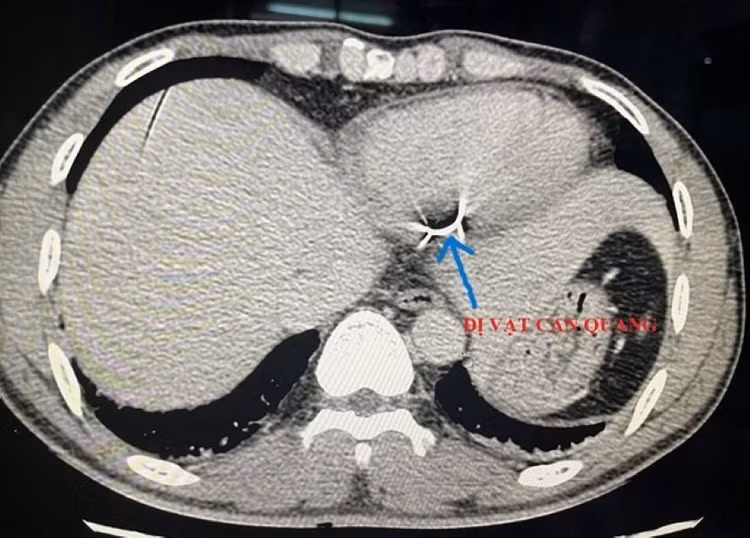

sat-trong-tim-1.jpg

Dị vật được lấy ra khỏi tim